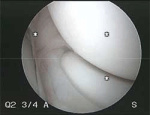

Elbow Arthroscopy